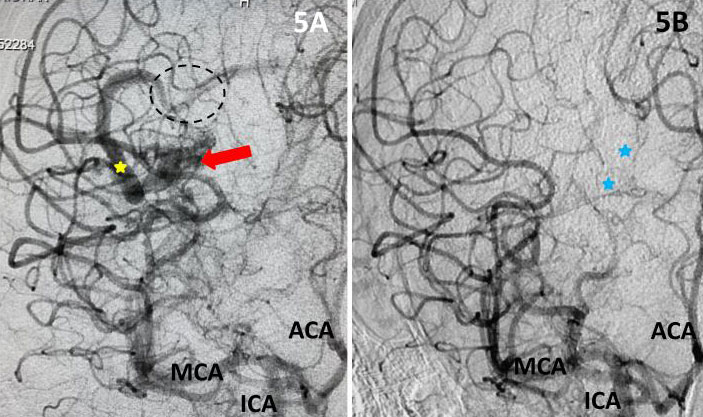

Fig 1. Head CT scan showing large right-sided, parieto-occipital intra-cerebral hemorrhage (ICH) and small occipital and temporal subdural hemorrhage (SDH) with right to left midline shift (red arrow).

A head CT revealed a large posterior-parietal intracerebral bleed, an acute subdural clot, and right to left midline shift (Fig 1). Following the review of a head CTA, the patient was diagnosed with a ruptured brain arteriovenous malformation (AVM). Urgent treatment was indicated for this acute intracerebral hemorrhage (ICH) with significant mass effect and the risk of catastrophic rebleeding of the AVM.